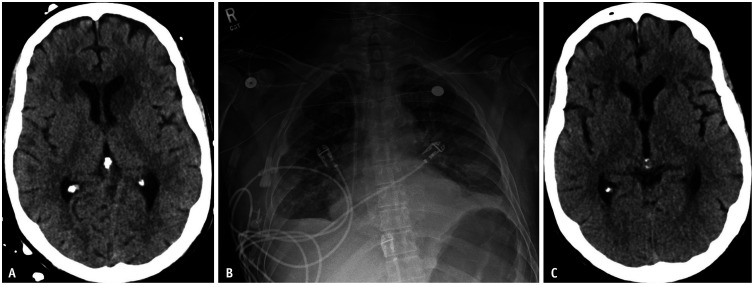

Clinical trials for chimeric antigen receptor (CAR) T-cell therapy are in the early stages but are expected to progress alongside new treatment approaches. This suggests that imaging will play an important role in monitoring disease progression, treatment response, and treatment-related side effects. There are, however, challenges that remain unresolved, regarding imaging in CAR T-cell therapy. We herein discuss the role of imaging, focusing on how tumor response evaluation varies according to cancer type and target antigens in CAR T-cell therapy. CAR T-cell therapy often produces rapid and significant responses, and imaging is vital for identifying side effects such as cytokine release syndrome and neurotoxicity. Radiologists should be aware of drug mechanisms, response assessments, and associated toxicities to effectively support these therapies. Additionally, this article highlights the importance of the Lugano criteria, which is essential for standardized assessment of treatment response, particularly in lymphoma therapies, and also explores other factors influencing imaging-based evaluation, including emerging methodologies and their potential to improve the accuracy and consistency of response assessments.